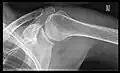

- Transaxillary projection

The arm should be abducted 80 to 100 degrees. This method reveals:[26]

- The horizontal alignment of the humerus head in respect to the socket and the lateral clavicle in respect to the acromion

- Lesions of the anterior and posterior socket border, or of the tuberculum minus

- The eventual non-closure of the acromial apophysis

- The coraco-humeral interval

Transaxillary conventional radiography -